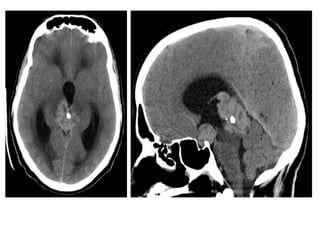

3-Choriocarcinoma, Yolk Sac Tumors and

Embryonal Carcinoma :

-Are rare neoplasms

-These neoplasms may have imaging findings

similar to those of other germ cell neoplasms or

primary pineal neoplasms

-Evaluation of tumor markers assists in making the

appropriate diagnosis

-These lesions may also hemorrhage - resulting in

T1 shortening

a)Sagittal T1 weighted MR

image shows an

heterogeneous pineal region

mass with foci of T1

shortening due to

hemorrhage , note the

associated hydrocephalus

b)Axial postcontrast T1-

weighted MR image shows

that the pineal region mass

also has an heterogeneous

enhancement with foci of

necrosis/cyst , involvement of

the tectal plate and both

thalami are also present (not

shown) , evaluation of serum

oncoproteins demonstrated

high level of b-hCG , biopsy of

the lesion revealed that it

corresponds to

Choriocarcinoma

a)Sagittal T1 weightedMR image shows an heterogeneous pineal region mass with foci of T1 shortening due to hemorrhage , note the associated hydrocephalus b)Axial postcontrast T1- weighted MR image shows that the pineal region mass also has an heterogeneous enhancement with foci of necrosis/cyst , involvement of the tectal plate and both thalami are also present (not shown) , evaluation of serum oncoproteins demonstrated high level of b-hCG , biopsy of the lesion revealed that it corresponds to Choriocarcinoma